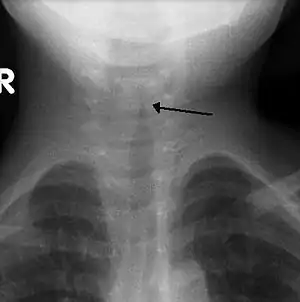

Radiografia gâtului nu este un procedeu de rutină,[6] însă dacă se realizează, poate indica îngustarea traheii, denumită semnul clopotului, datorită formei de clopot a acesteia. Aspectul de clopot nu este evident în jumătate din cazuri.[5]